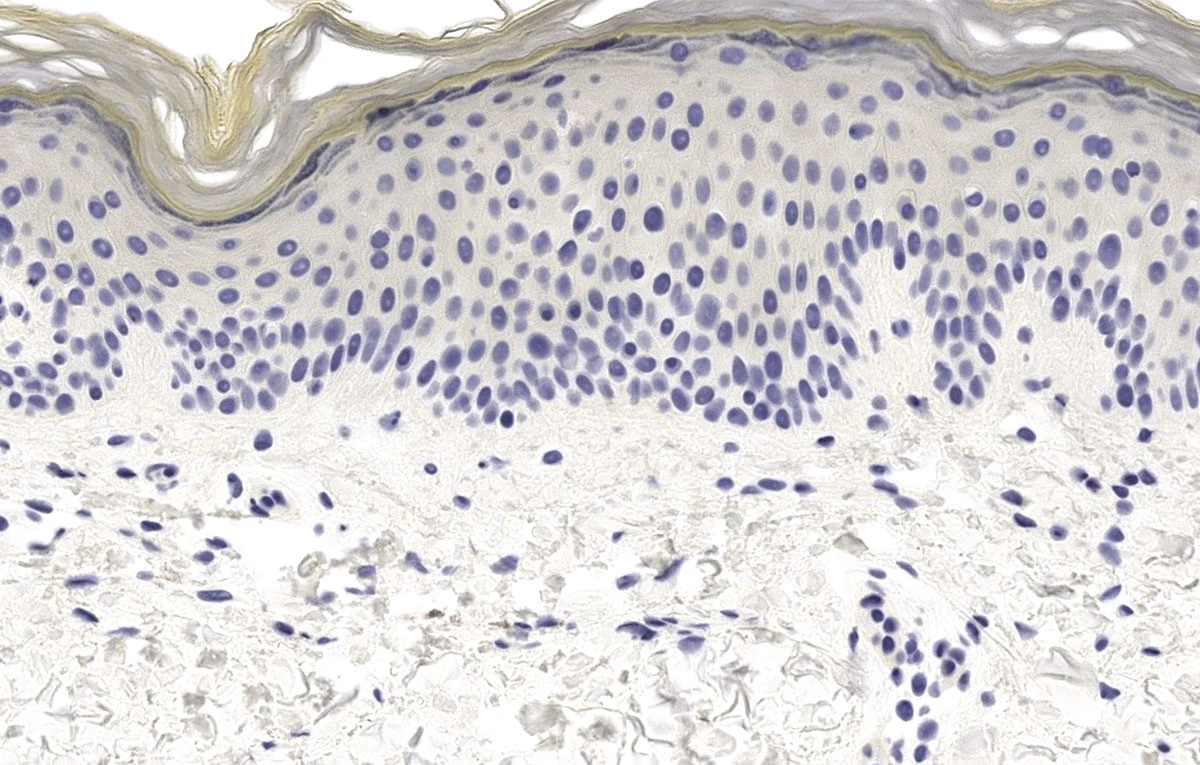

Inmunohistoquímica

- Módulo 1: Generalidades

- Módulo 2: Técnica

- Módulo 3: Usos en dermatopatología

- Módulo 4: Lista de anticuerpos de uso frecuente